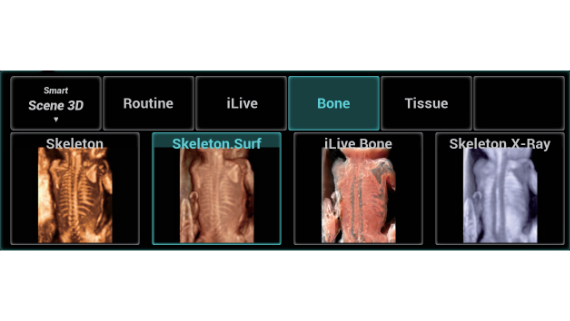

Nuewa I9? ??? ???? ?? ??? ?? ??? ???? ?? ??? ???? ???? ??? ?????. ??? ??? ??? ?? ????? ?? ???? ???? ???? ???? ??? ???? ??? ??? ???? ??? ???? ??? ?? ?????.